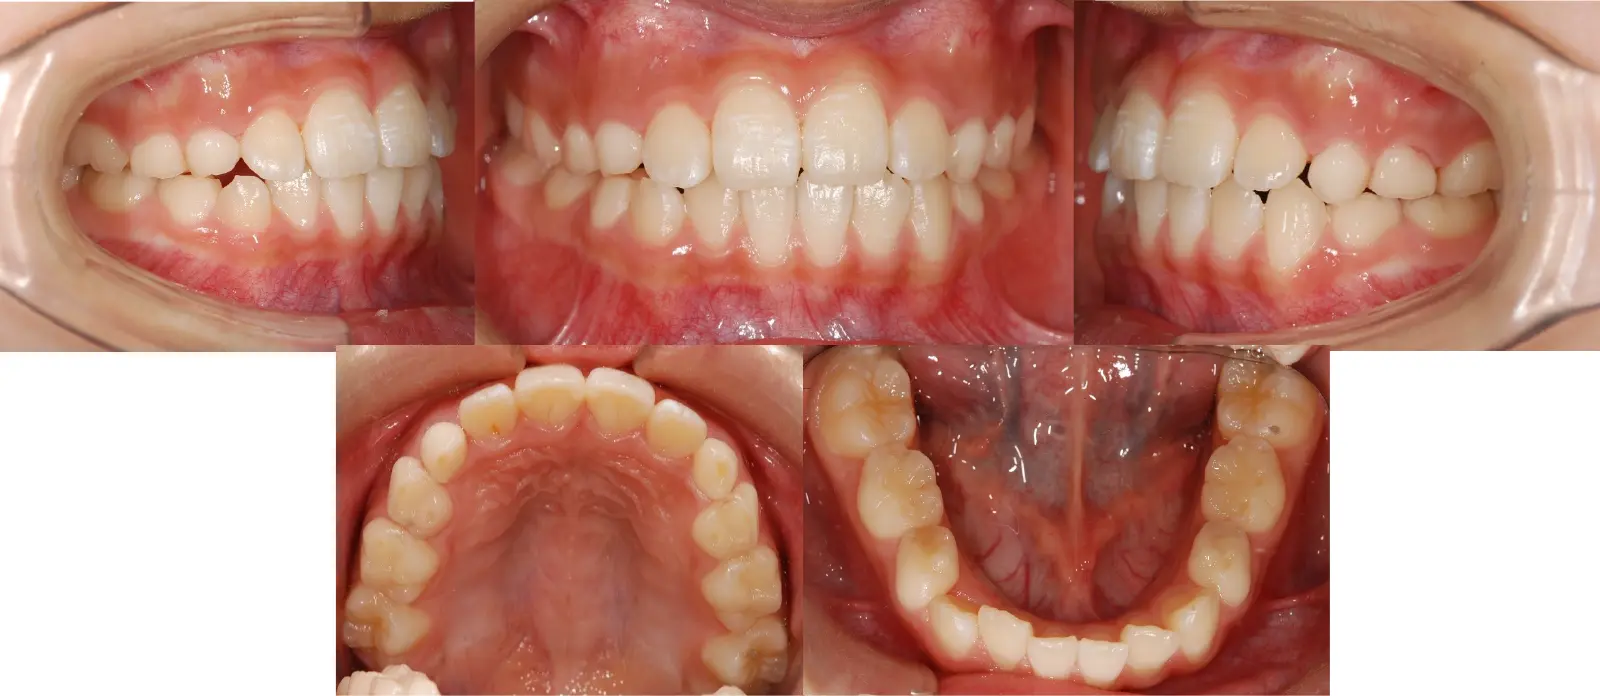

1歯のみの反対咬合

第一段階の治療のみで、

永久歯は問題なく萌出し、安定している

- 主訴

1歯のみの逆破蓋

- 年齢

8歳

- 治療期間

7ヶ月

- 治療回数

5回

- 治療に用いた主な装置

拡大床

- 治療費

400,000円(税別)トータル料金